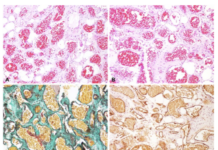

El informe histopatológico, reveló microscópicamente la presencia de una lesión polipoidea revestida de epitelio escamoso sin atipias y subyacentemente ocupando la totalidad del corion una proliferación difusa sin formación de plexos , constituida por células de citoplasma mal definido y bordes mal delimitados que contienen unos núcleos pequeños ondulados y con proliferación fibrilar, siendo el diagnóstico de neurofibroma solitario (Figura 6-8).